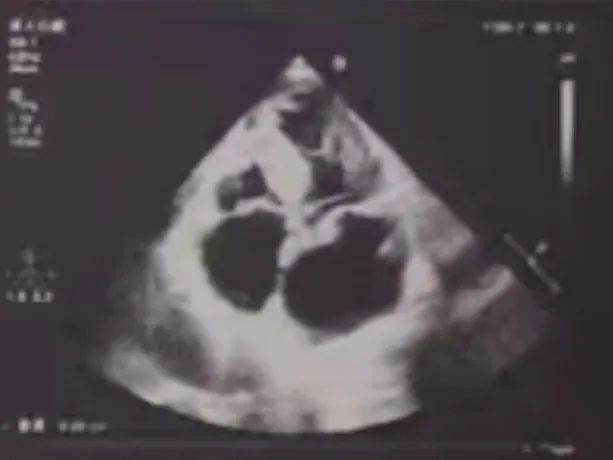

珠海市人民医院超声科张恒教授术中使用食道超声评估瓣膜形态、瓣膜植入深度、反流及瓣周漏情况

术后评估

术后超声:峰值流速1.06m/s,跨瓣压差6mmHg

瓣膜释放位置佳,释放后瓣膜工作正常,无明显瓣周漏及传导阻滞情况。患者的平均跨瓣压差由术前的50mmHg改善至术后的6mmHg, 主动脉瓣瓣口峰值流速由术前的5.1m/s改善至术后的1.06m/s,患者获益明显。